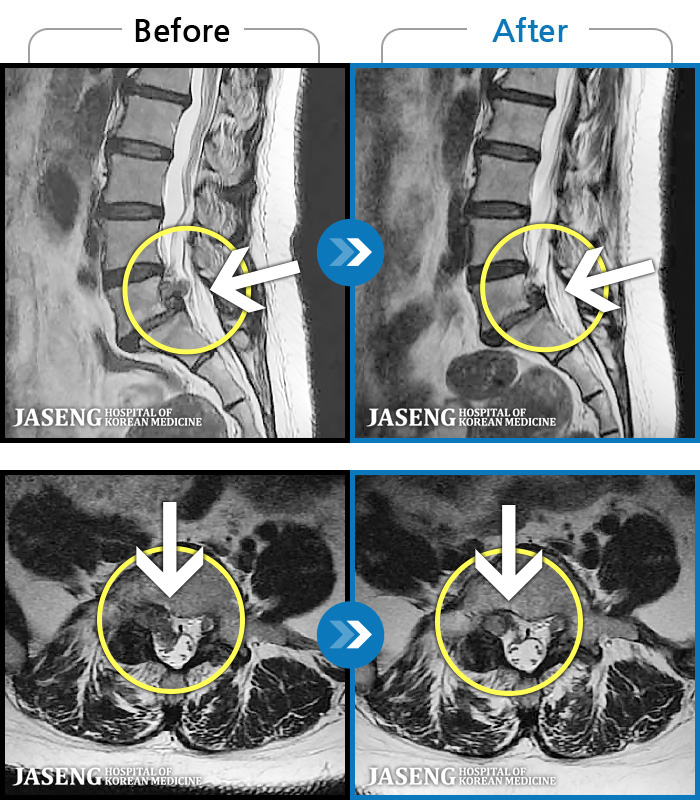

MRI ġ

119 MRI ũ ʸ Ȯϼ.

[Կñ:24.01.30~24.07.09]

[_㸮ũ] ٸ ؼ ɾٴϱ

No.119

ȸ 599

2024.12.24